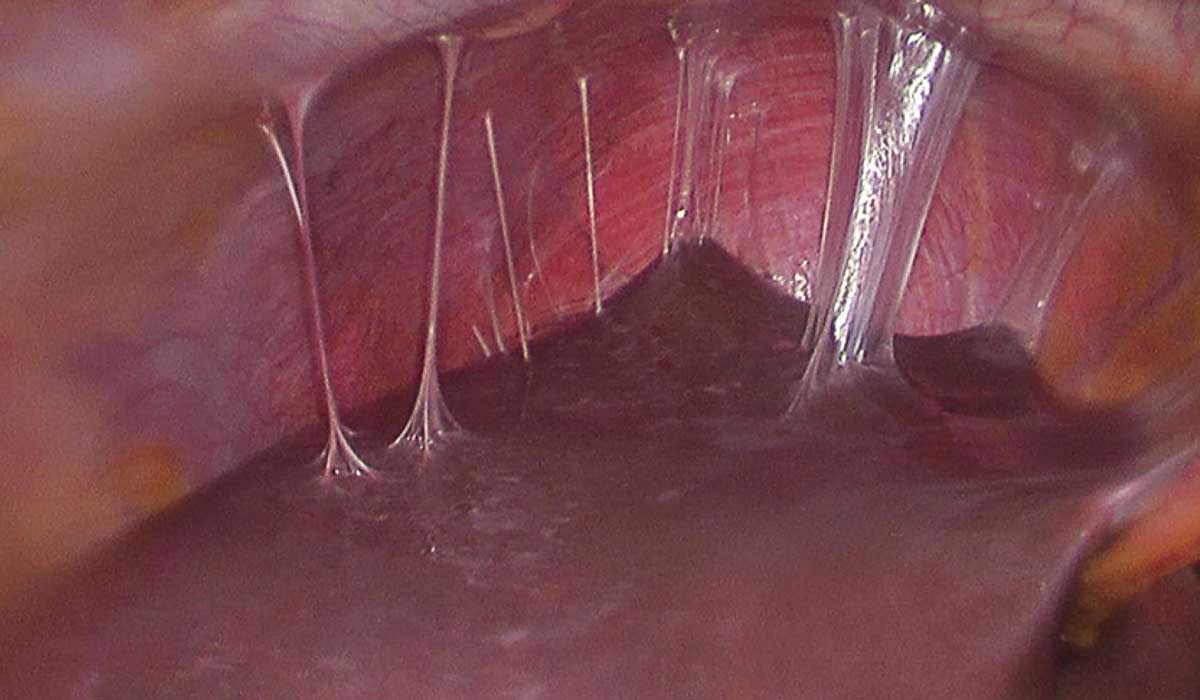

با ابراز سرفه خلطدار، این سوال تکراری در ذهن همه ما وجود دارد؛ برای سرفه خلط دار چه شربتی خوبه؟ شربت اکسپکتورانت با رقیقکردن مخاط علتمیبشود که گلو راحتتر از مخاط و خلط پاک بشود. از اکسپکتورانتها برای درمان علائم عفونتهای دستگاه تنفسی منفعت گیری میبشود. این نوع عفونتها شامل سرماخوردگی، برونشیت و ذاتالریه می باشند و میتوانند جهت تجمع مخاط در گلو و ریهها شوند. امکان پذیر، به علت تجمع مخاط دچار سرفه شوید و سینه شما درد بگیرد. اکسپکتورانتها به تسکین این علائم پشتیبانی میکنند. از اکسپکتورانتها برای تسهیل سرفه خلطدار منفعت گیری میبشود. طبق معمول مصرف اکسپکتورانت،برای افت خلط از سوی پزشکان تجویز میبشود. دقت کنید که بعضی اوقات سرفه شرایط پیچیدهای دارد. برای مثال، سرفه خلطدار خونی نشانه چیست؟ این حالت میتواند حکایت از ابتلا به بیماریهای زیاد جدی داشته باشد و دیگر نمیتوانید این چنین موردی را با اکسپکتورانت و داروهای بینسخه کنترل کنید. در این صورت باید به دکتر گوش مراجعه کنید تا تشخیص دهند و درمان را اغاز کنند.